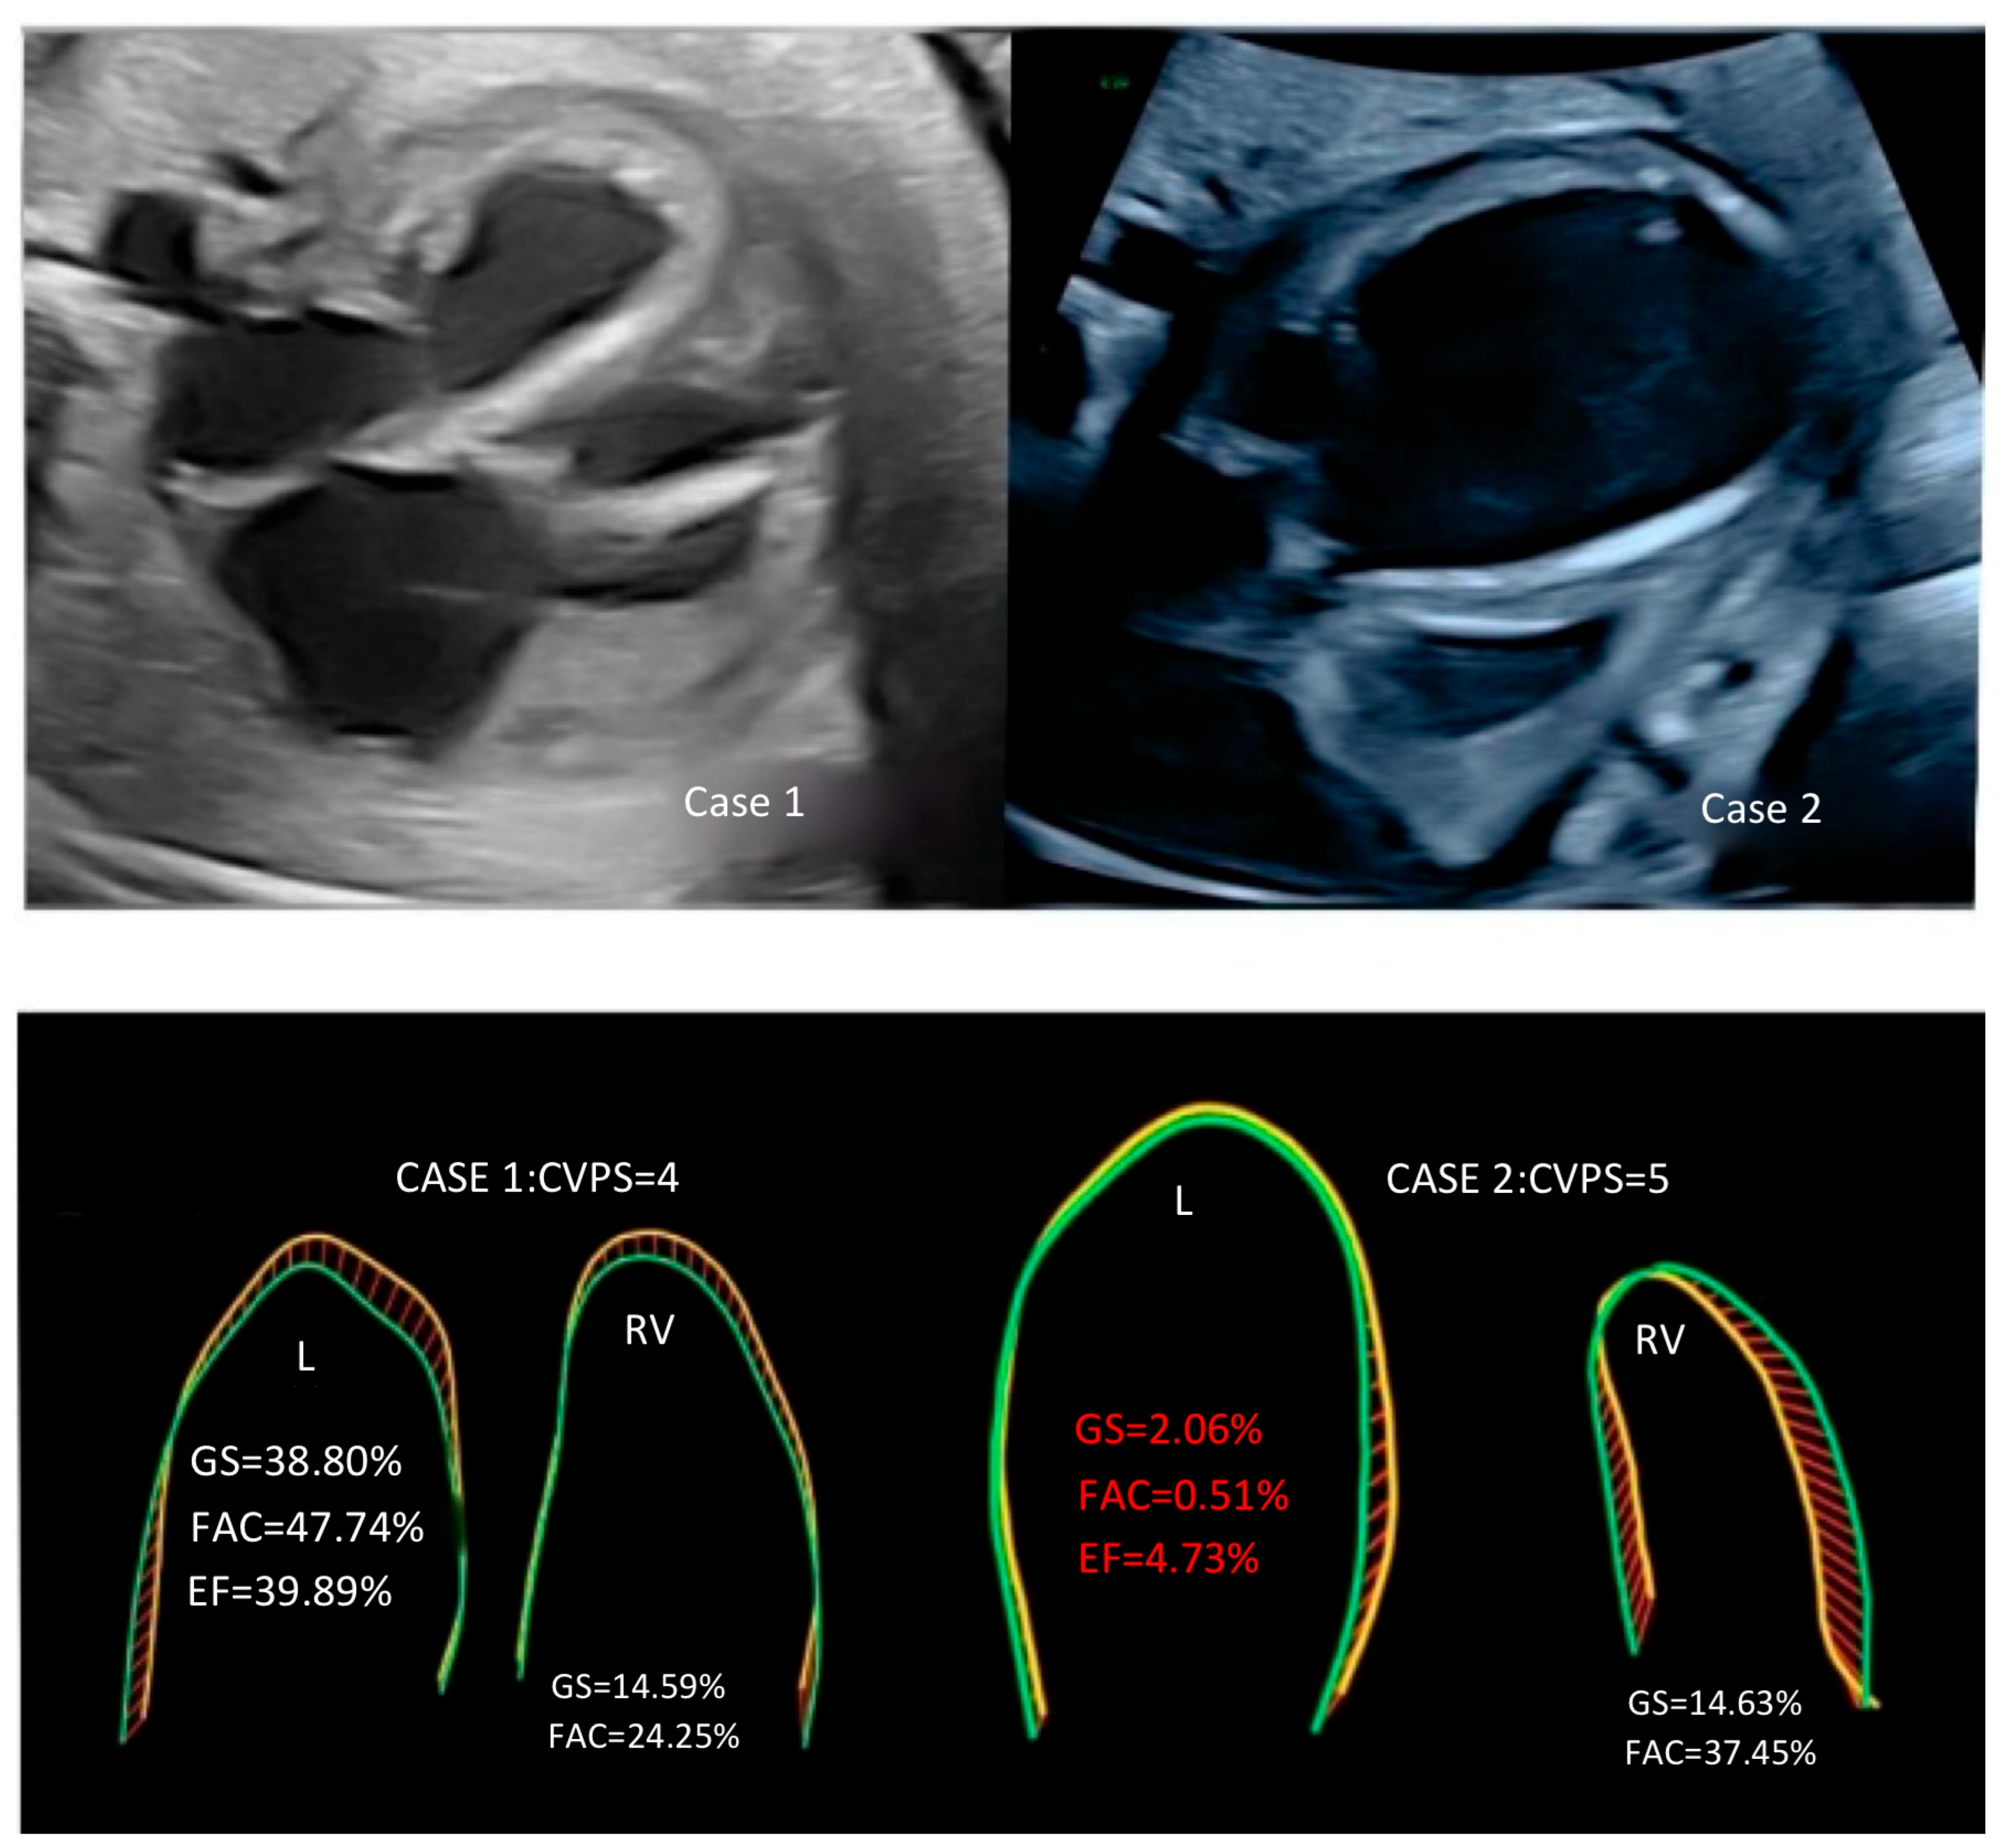

| CVPS points | 4 | 5 |

| M—mode EF [%] | 40 | 5 |

| Global strain LV [%] | −38.80 | −2.06 |

| Frac. area change LV [%]—fractional area change | 47.74 | −0.51 |

| EF LV [%]—ejection fraction for left ventricle | 39.89 | 4.73 |

| Global strain RV [%] | −14.59 | −14.63 |

| Frac. area change RV [%]—fractional area change | 24.25 | 37.45 |